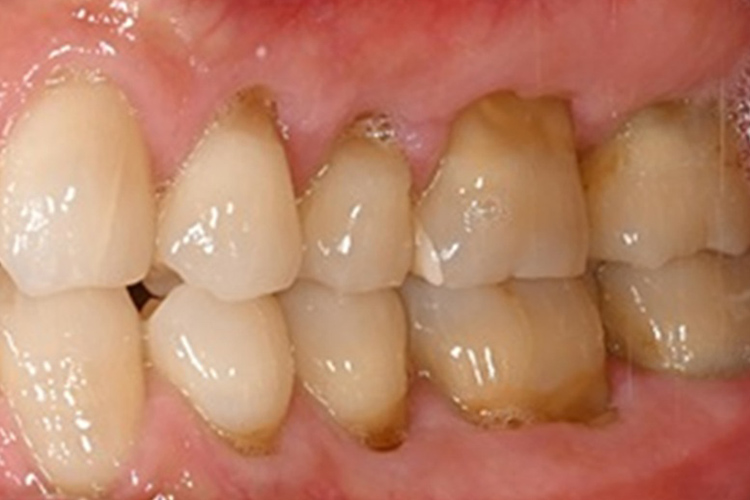

実施例①

この患者様は、口腔内全体において重度の歯周病が生じており、歯磨き指導、クリーニング、Flap手術等を行ったが、歯周ポケットが深すぎるためブルーラジカル適用症例と診断し、施術を行いました。

実施前

施術前のレントゲンと口腔内写真です。施術前にプラークの除去を行ってから、施術します。